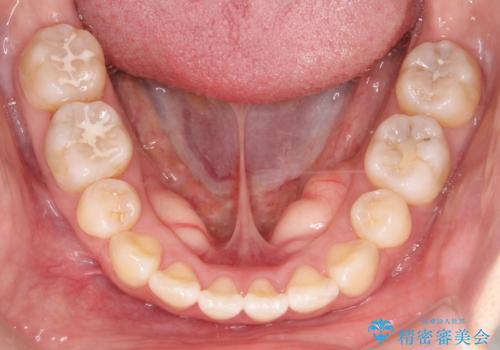

- ”口元を下げたい”が主訴で来院されました。

抜歯してワイヤー矯正を行い、口元も改善され大変満足していただきました。

小臼歯の抜歯を行うことで口元を改善することができました。